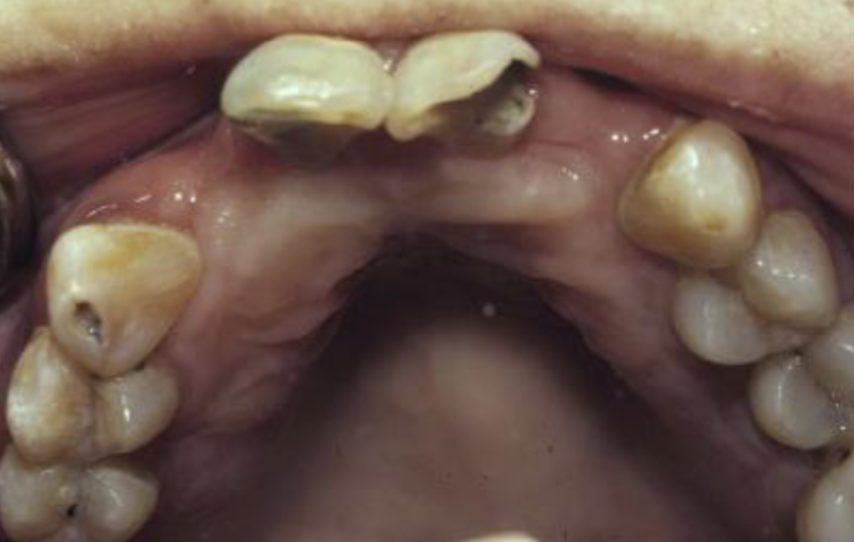

16

Q

How would you describe this image?

A

Gross coronal decay